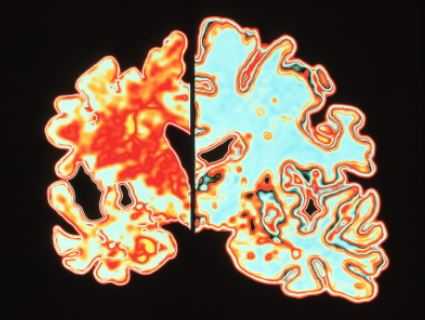

МРТ головного мозга. Демонстрация атрофии и нормы при цветовой обработке.

Под термином “нейродегенеративные заболевания” (НДЗ) определяется большая группа заболеваний преимущественно позднего возраста, для которых характерна медленно прогрессирующая гибель определенных групп нервных клеток и одновременно - постепенно нарастающая атрофия соответствующих отделов головного и/или спинного мозга. В основе развития этих заболеваний лежит нарушение метаболизма и изменение конформации клеточных белков с их последующим накоплением и агрегацией в определенных группах нейронов. При НДЗ страдают преимущественно нейроны и глиальные клетки базальных ганглиев и стволовых структур, вырабатывающие ацетилхолин, дофамин, серотонин.

Болезнь Альцгеймера - прогрессирующее нейродегенеративное заболевание, характеризующееся постепенным развитием деменции. Происхождение заболевания точно неизвестна. Биохимические изменения состоят в снижении активности холин-ацетил-трансферазы коры головного мозга и гиппокампов. Патологические проявления заключаются в образовании специфических амилоидных бляшек, нейрофибриллярных тяжей и реактивном глиозе. Развивается атрофия, захватывающая преимущественно кору вокруг Сильвиевых щелей и гиппокампы, с вторичным расширением желудочков, особенно височных роговЗаболевание впервые описано Alois Alzheimer в 1907 году. Процесс напоминает естественное старение, но резко ускоренное. Начинается с нарушений памяти, затем потерянность, невозможность повседневного самообслуживания, повторяющиеся вопросы. Позже присоединяются глубокие нарушения психики, речи, потеря веса, судороги.

Частота составляет 0,51% для лиц в возрасте 70-74 лет с возрастным прогрессирующим увеличением частоты. Клинические проявления состоят в нарушении памяти, депрессии, поведенческих нарушениях и галлюцинациях. На поздних стадиях к психическим расстройствам добавляется экстрапирамидная симптоматика. Заболевание занимает 4 место по смертности. Диагноз ставится на основании клинического и нейрофизиологического обследования, а также нейровизуализации. Типичные проявления на КТ состоят в диффузной атрофии (особенно,височных долей), вторичном расширении борозд и желудочков. Чувствительность КТ (без измерения объемов) в сравнении с нормальной возрастной группой около 80%, специфичность около 70%. Измерение объемов гиппокампов при выполнении МРТ с тонкими срезами повышает точность до 85%.

МРТ головного мозга служит метода выбора оценки структурных изменений. Атрофические изменения выражены во всём медиобазальном отделе височной доли. Чувствительность и специфичность МРТ при начальной деменции около 80%. Измерение объемов гиппокампов и амигдалы повышает точность до до 85%.